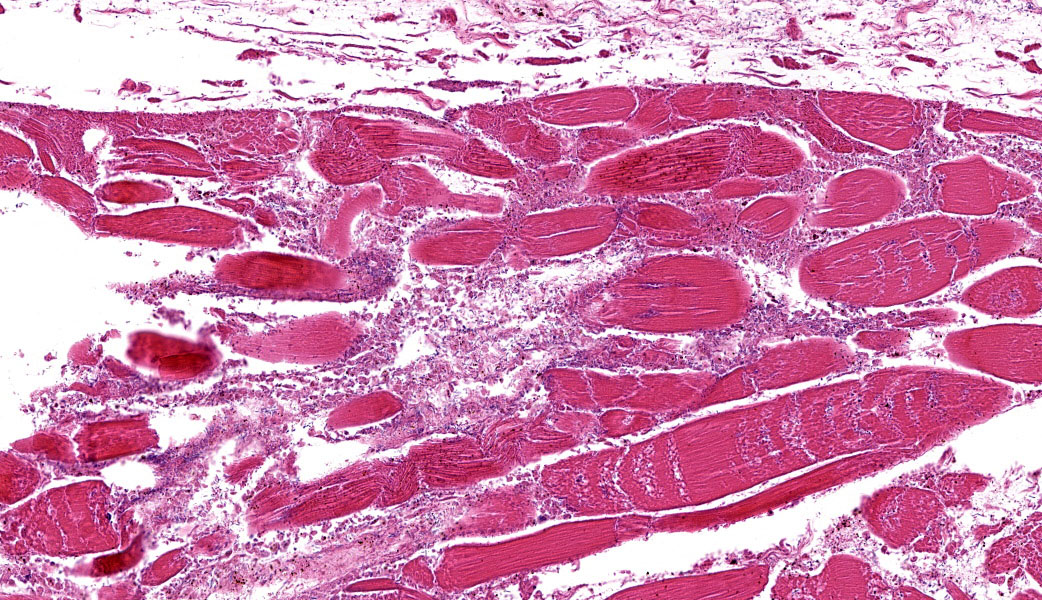

Microscopic Description:

The grossly affected skeletal muscle is necrotic with swollen, hypereosinophilic to pale staining myofibers that have lost their cross striations. The sarcoplasm of small numbers of myofibers is fragmented and replaced by eosinophilic flocculent material. The interstitium is emphysematous and contains small amounts of hemorrhage and edema that separate individual myofibers and the endomysium. There are also numerous large bacilli and a few perivascular to random multifocal infiltrates of small numbers of degenerate neutrophils in the interstitium. There are small numbers of arterioles and venules with necrosis of the vascular wall.

Skeletal muscle: Acute necrosis with emphysema, hemorrhage, mild suppurative myositis and numerous intralesional bacilli; etiology, Clostridium novyi.

Clostridial myonecrosis can develop in multiple species, but is most common in ruminants, horses, and swine.3 In all species, skeletal muscle necrosis in the primary lesion. The muscle necrosis is accompanied by edema, hemorrhage, and often emphysema. The hemorrhage and lysis of erythrocytes cause the affected skeletal muscle to be dark red to black.

The necrotic skeletal muscle often has a rancid odor. The microscopic lesions mirror the gross lesions. The primary microscopic lesion is necrotic myofibers that are separated by edema, hemorrhage and lysed erythrocytes. The skeletal muscle may be emphysematous. There typically are very few neutrophils within the lesion. The number of bacteria in the lesion varies widely with the lesions in some animals containing large numbers of bacteria with the lesions in other animals containing small numbers of bacteria. Most lesions have small numbers of bacteria. Fragmentation of the necrotic myofibers in the deeper aspects of the lesions may be present. The affected animals die quickly usually within twenty-four hours if not treated. The histotoxic clostridia spread quickly throughout the carcass postmortem resulting in rapid decomposition. Because these bacteria spread quickly throughout the carcass postmortem, one has to be careful in interpreting positive identification of histotoxic clostridia within muscle lesions as the Clostridium species identified may be a postmortem contaminant rather than the cause of the muscle necrosis.